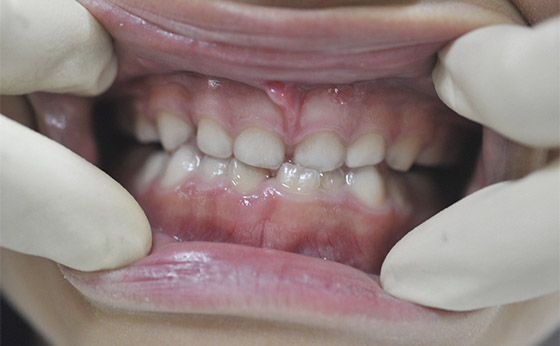

症例03 - ムーシールドによる歯列矯正

途中経過01

5歳の女の子、来院時、ご覧のような反対咬合。

下の歯が上の歯に逆に被さっています。ムーシールドという矯正装置を夜寝るときだけ装着しました。

途中経過02

4か月でここまで改善しましたが、左の前歯だけが反対に噛んでます。